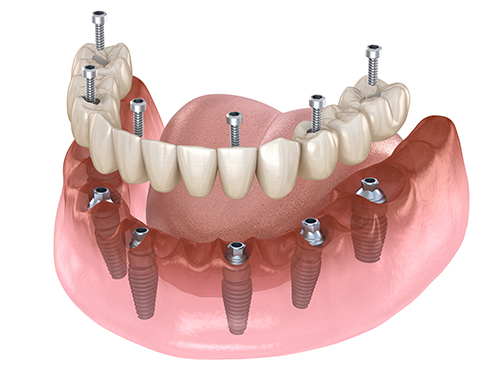

そもそもオールオン4とは

しかしオールオン4は4本のインプラントを埋め込むだけなので、治療費は200万円ほどで済みます。ただオールオン4も一般的なインプラントも治療費は歯科クリニックによって大きく異なるので、事前に確認することをおすすめします。

人工歯根(インプラント)を埋め込む

まず歯肉を切開し、顎の骨を露わにします。電動やすりで顎の骨の上面を平らにした後で、小さなドリルを使って顎の骨に4本の穴をあけていきます。この穴に人工歯根(インプラント)を埋め込んでいくわけです。

支台装着

人工歯根を埋め込んだら、その上端に「支台」という金具を装着します。この支台は人工歯根と「12本の連なった人工歯(オールオン4)」を結合させるためのものです。この後、切開した歯肉を縫うのですが、そのとき支台は歯肉の上に出るようにしておきます。